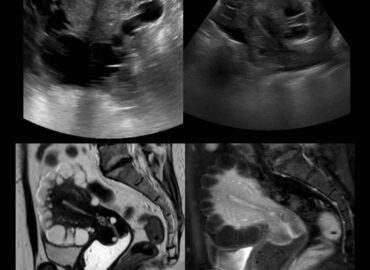

Mujer de 41 años, deportista profesional (remo) con dolor e induración en región coccigea y perianal a la sedestación. […]